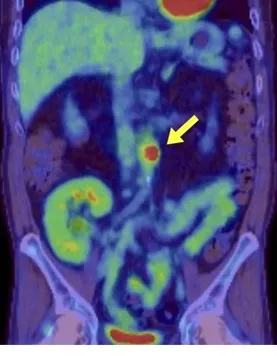

Uma causa incomum de hematúria glomerular intermitente!

Uma causa incomum de hematúria glomerular intermitente!

Hematúria pós infecção, caso clínicos para auxiliar no entendimento de causas glomerulares comuns e raras...